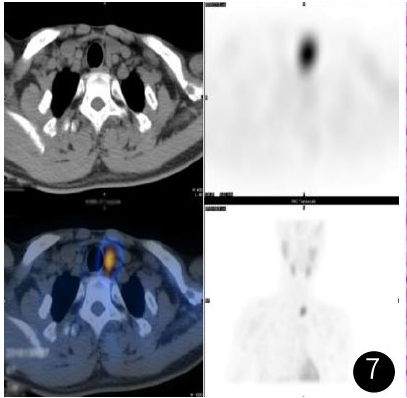

X线提示:左肱骨骨质破坏并肿物形成。增强CT提示:左肱骨骨质破坏并软组织肿物形成,增强呈明显强化,余多处骨质破坏、骨质疏松改变。甲状腺左侧叶下方结节,增强呈明显强化。增强MR提示:左肱骨骨质破坏并肿物,T1WI呈等信号,T2压脂序列呈不均匀高信号为主,其内呈多发囊状改变,增强扫描呈不均匀明显强化,周围软组织水肿

图1-图2 CT平扫及增强:左肱骨骨质破坏并等密度肿物,增强扫描呈明显强化。